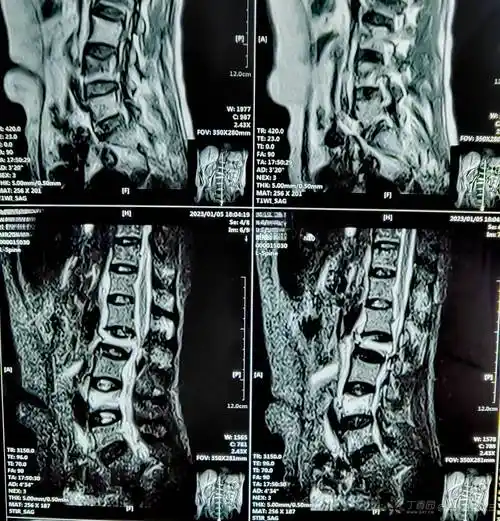

超能刀客止麻先锋故事会│009号腰痛的故事

2020年12月20日疼痛科完成一例椎间孔镜下l4/5椎间盘突出髓核摘除术